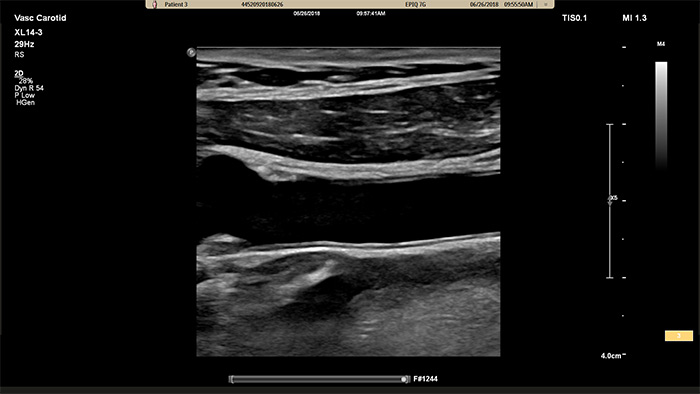

XL14-3 xMATRIXトランスジューサは、実に56,000素子を配列し、すべて別のマイクロチャネルに接続されています。XL14-3トランスジューサは、血管構造およびプラーク形態を描出するための薄いスライスと多段フォーカス機能を備えています。主なメリットは、狭窄や不安定プラークを評価する際の診断確度の向上があります。

XL14-3 xMATRIXトランスジューサは、縦断面および横断面を同時にリアルタイムで描出して血管検査の標準アプローチを超える、xPlaneイメージングを提供します。xPlaneイメージングの主なメリットとして、トランスジューサを回転することなく直交断面を収集できる点が挙げられます。トラックボールのシンプルな動きで、完全な解剖学的評価を提供し、検査時間を短縮できます。